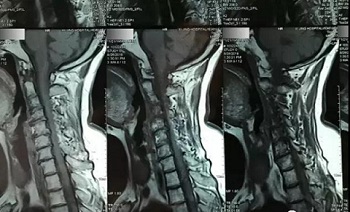

十一、将分区的磁共振图像,按顺序进行拍摄,即可获取如下比较有价值的清晰图片

(区域4)

(区域5)

(区域6)